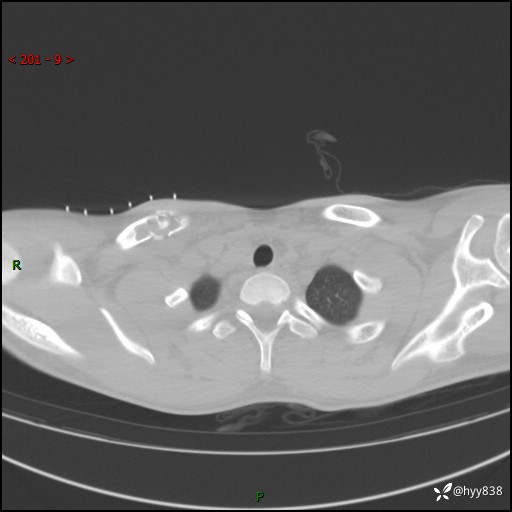

CT